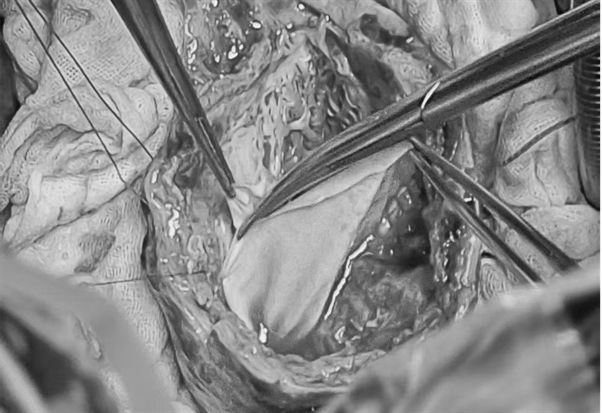

手术在全身麻醉体外循环下进行,总时长 497 分钟,体外循环 224 分钟,主动脉阻断 137 分钟。术中探查见心肌极薄,室壁瘤区域形成心外膜夹层样改变,夹层内广泛血栓形成,采用 保留部分外膜包裹缝合 技术,既彻底切除病变室壁瘤组织及血栓,又通过分层全程缝合技术将左心室重塑为接近正常的几何形态。

LVAD 植入时,反复试探流入管位置,确保固定于相对正常的心肌区域,避免因心肌薄弱导致的泵血栓或脑血管事件;流出管选择主动脉右前方,距瓣环 4 公分处植入,保证血流动力学稳定。

室壁瘤缝合后心室腔较小,特选用无插入式血管型人工心脏,不深入心室,避免抽吸室间隔或心室壁,降低触碰心室壁引发心律失常,也可避免因心室空间狭小,引起楔形血栓的风险,同时保持左心室完整的球形结构,保持良好的血流涡旋。